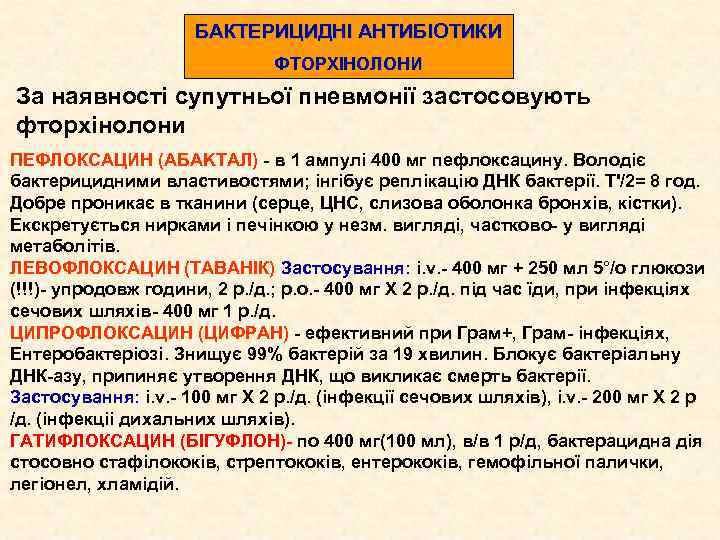

БАКТЕРИЦИДНІ АНТИБІОТИКИ ФТОРХІНОЛОНИ За наявності супутньої пневмонії застосовують фторхінолони ПЕФЛОКСАЦИН (AБAKTAЛ) - в 1 ампулі 400 мг пефлоксацину. Володіє бактерицидними властивостями; інгібує реплікацію ДНК бактерії. Т'/2= 8 год. Добре проникає в тканини (серце, ЦНС, слизова оболонка бронхів, кістки). Екскретується нирками і печінкою у незм. вигляді, частково- у вигляді метаболітів. ЛЕВОФЛОКСАЦИН (ТАВАНІК) Застосування: i. v. - 400 мг + 250 мл 5°/о глюкози (!!!)- упродовж години, 2 p. /д. ; р. о. - 400 мг Х 2 p. /д. під час їди, при інфекціях сечових шляхів- 400 мг 1 p. /д. ЦИПРОФЛОКСАЦИН (ЦИФРАН) - ефективний при Грам+, Грам- інфекціях, Ентеробактеріозі. Знищує 99% бактерій за 19 хвилин. Блокує бактеріальну ДНК-азу, припиняє утворення ДНК, що викликає смерть бактерії. Застосування: i. v. - 100 мг Х 2 р. /д. (інфекції сечових шляхів), i. v. - 200 мг Х 2 р /д. (інфекціі дихальних шляхів). ГАТИФЛОКСАЦИН (БІГУФЛОН)- по 400 мг(100 мл), в/в 1 р/д, бактерацидна дія стосовно стафілококів, стрептококів, ентерококів, гемофільної палички, легіонел, хламідій.